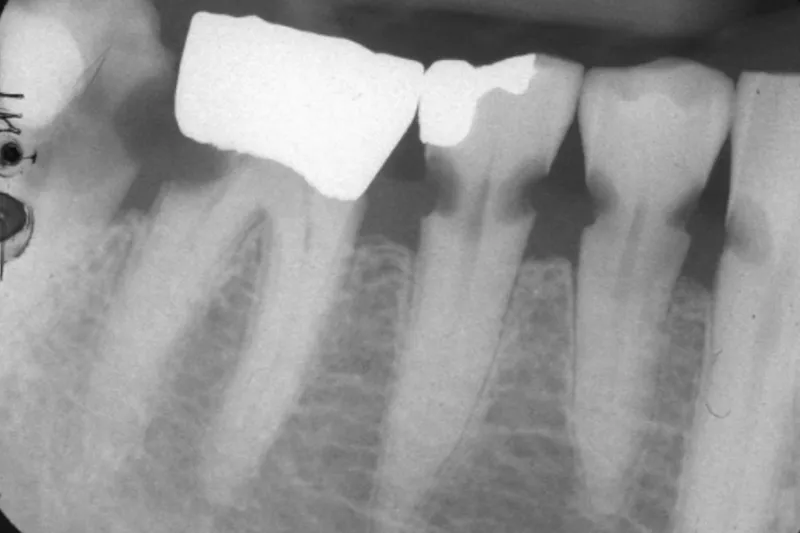

Flere ældre har behov for undersøgelse og behandling – fordi flere ældre med flere tænder fører til øget forekomst af orale sygdomme.

Så længe den almene og kognitive tilstand er god, opretholdes tandsundheden. Men med svigtende autonomi, polyfarmaci og nedsat spytfunktion kan den orale sundhed hurtigt forringes – i takt med at mulighederne for terapeutisk intervention forringes.

Tandtab er ikke aldersbetinget – men aldersrelateret. Ældre har en forøget risiko for at udvikle orale sundhedsproblemer. Det er væsentligt at identificere risikopatienter. Indsigt i, hvordan sygdomsrisiko varierer fra individ til individ, er grundlaget for et fleksibelt indkaldeinterval, som er baseret på den enkeltes behov (cariesaktivitet, almen sundhedstilstand, mundtørhed, evne til egenomsorg, komplicerede protetiske konstruktioner etc.). Oftest bliver udgifterne til reparation i form af menneskelige og økonomiske resurser betydeligt større end ved de forebyggende tiltag, som rutinerne beskriver. Konsekvenserne af manglende vedligeholdelse er velkendte: tab af tænder, dårligere oral og generel sundhedstilstand, social stigmatisering, ernæringsproblemer, smerter etc. Forebyggelse er bedst – og billigst.